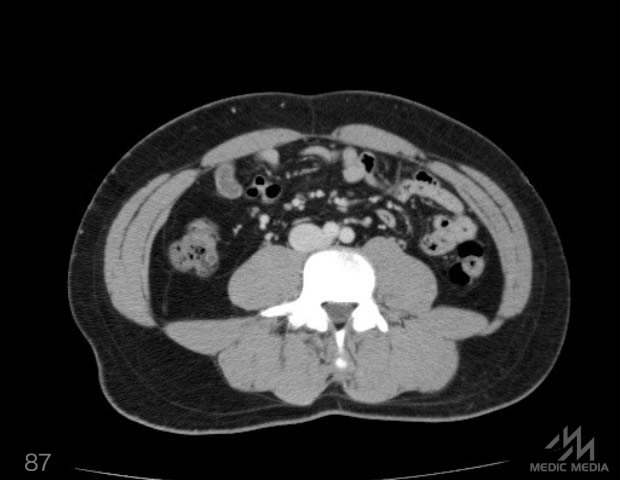

造影CT

消化器

肝区域